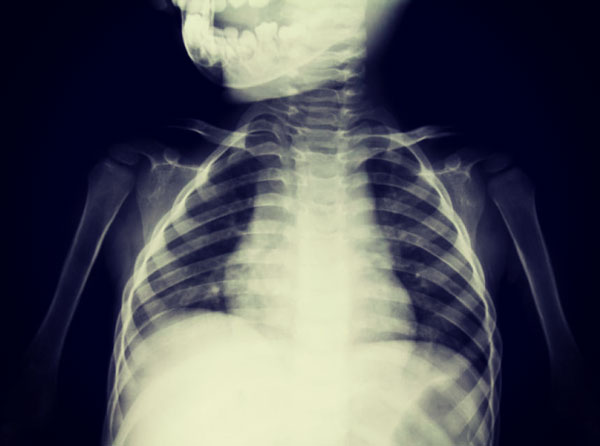

- Рентген;